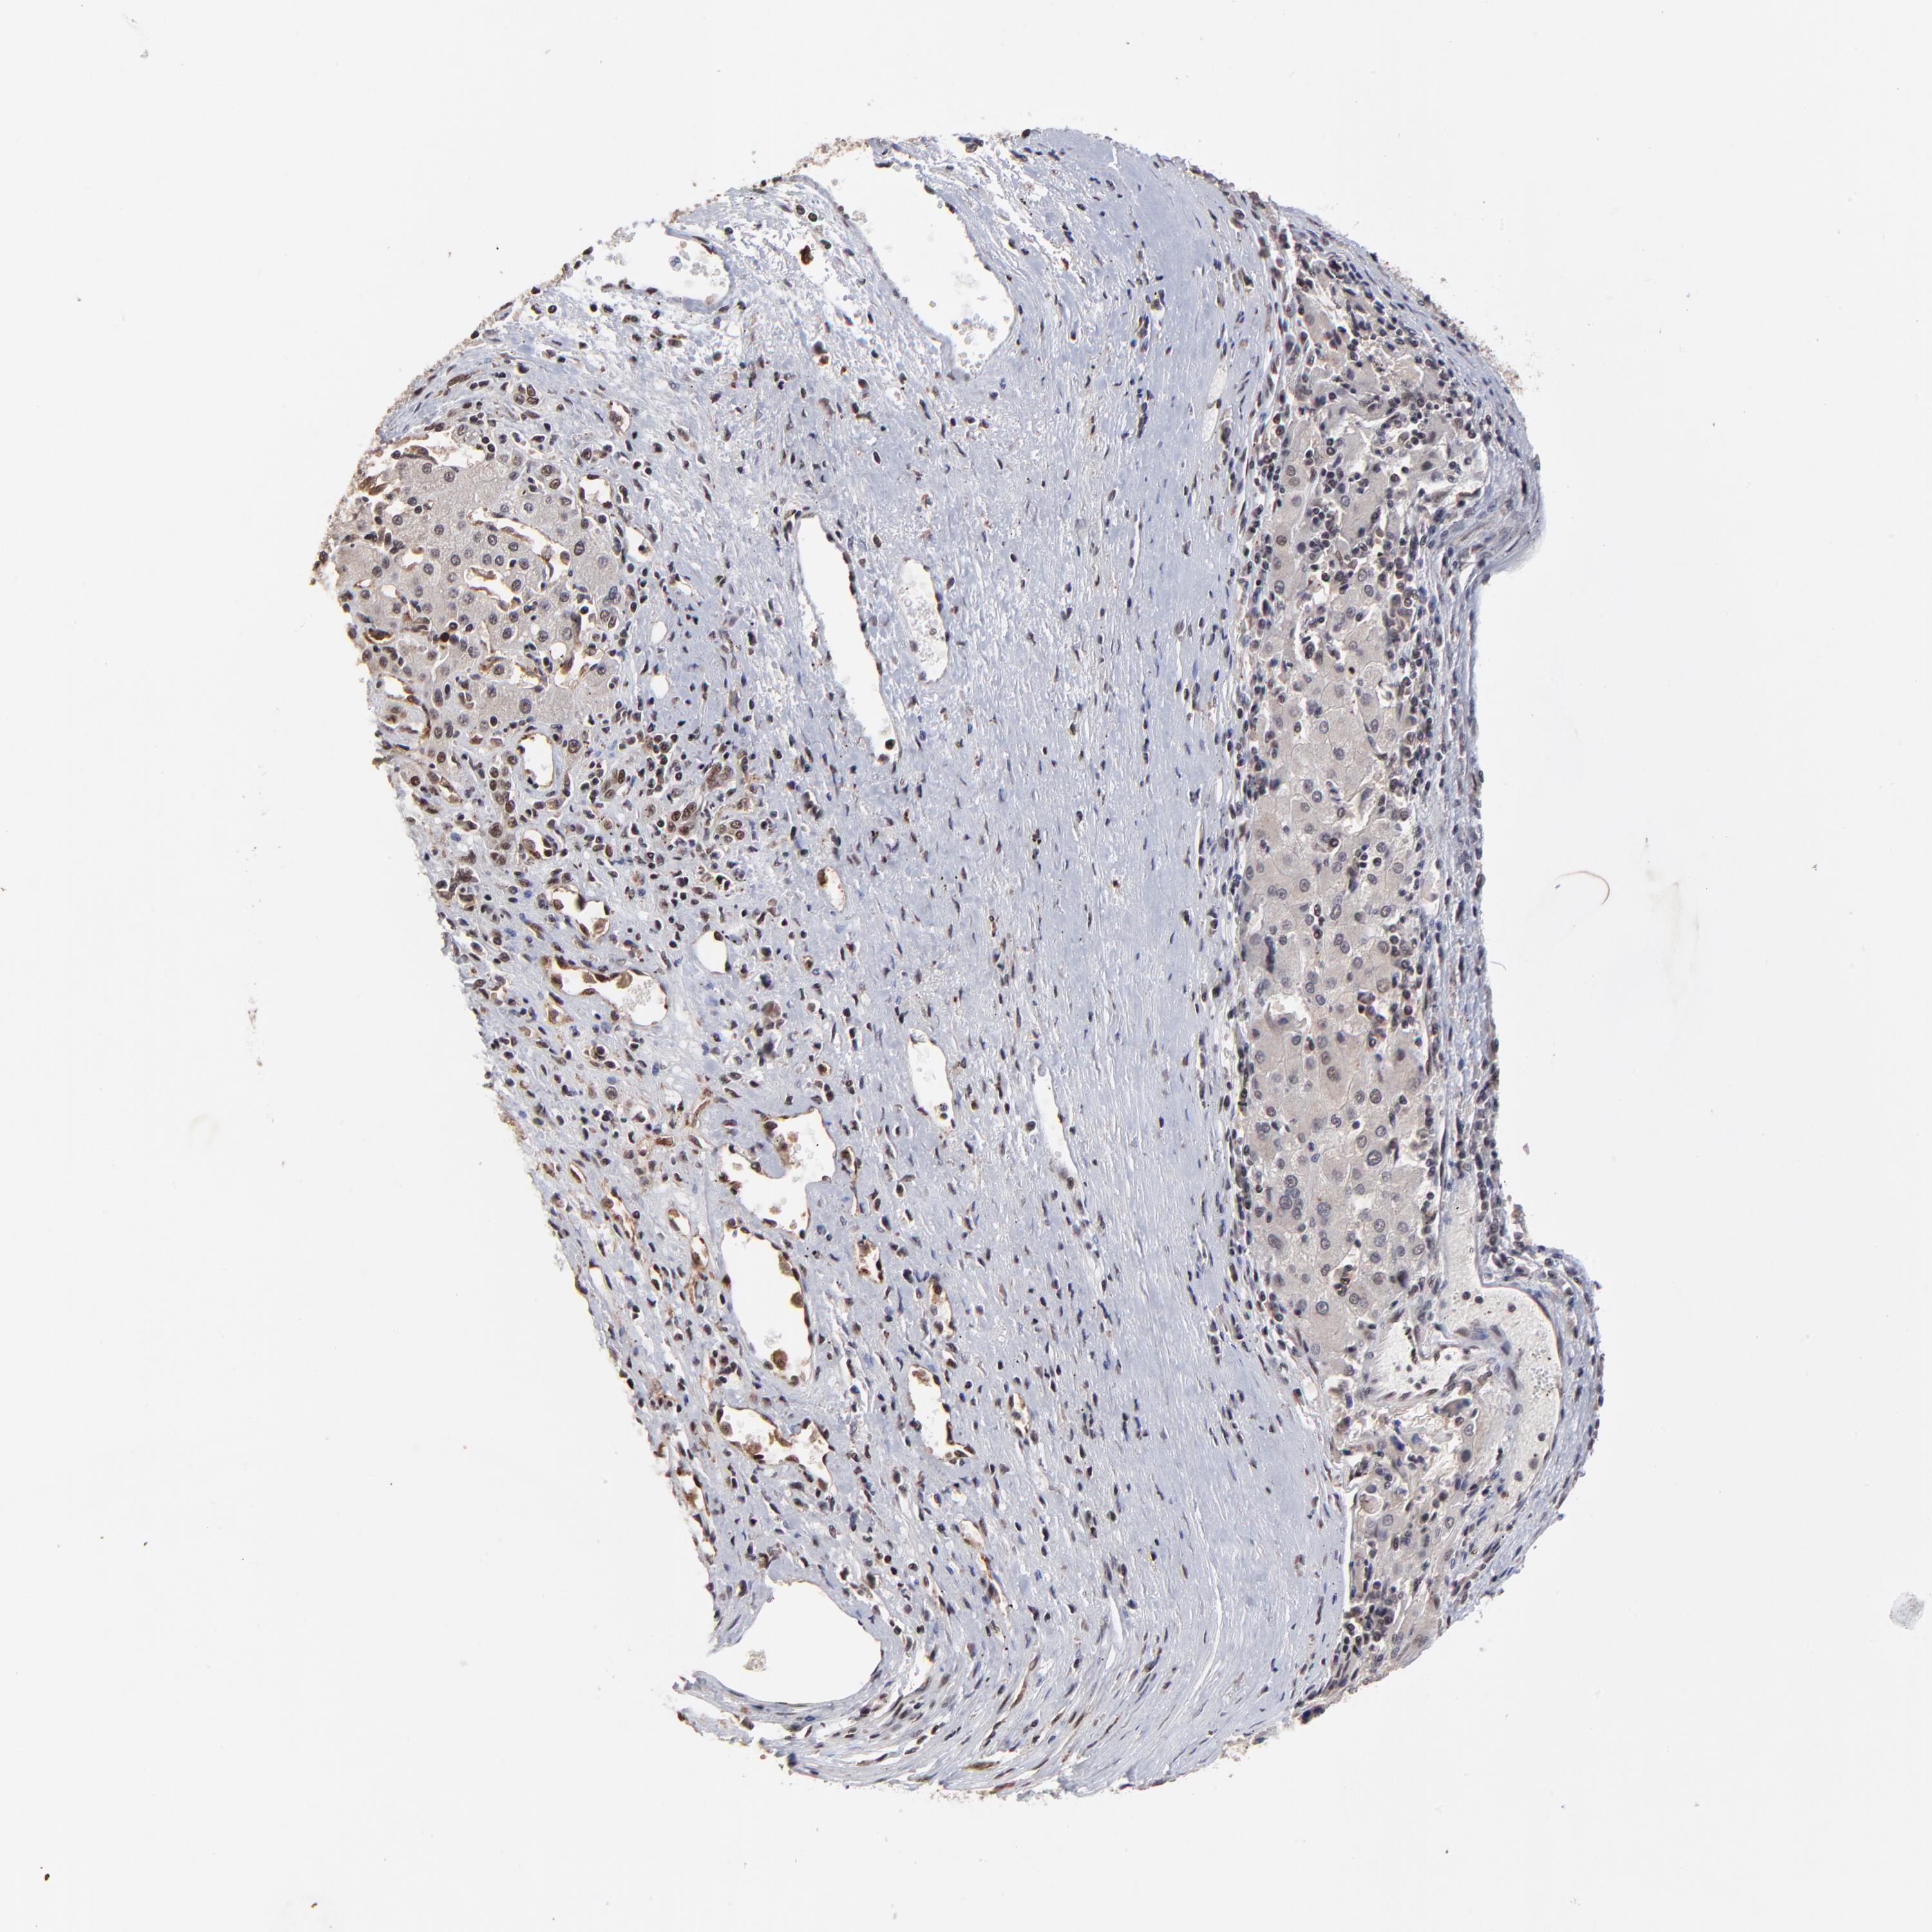

LIVER CANCER - Protein expressioni

A mouse-over function shows sample information and annotation data. Click on an image to view it in a full screen mode. Samples can be filtered based on level of antibody staining by selecting one or several of the following categories: high, medium, low and not detected. The assay and annotation is described here.

Note that samples used for immunohistochemistry by the Human Protein Atlas do not correspond to samples in the TCGA dataset.

Antibody stainingi

Antibody staining in the annotated cell types in the current human tissue is reported as not detected, low, medium, or high, based on conventional immunohistochemistry profiling in selected tissues. This score is based on the combination of the staining intensity and fraction of stained cells.

Each image is clickable and will lead to virtual microscopy that enables deeper exploration of all samples and also displays staining intensity scores, fraction scores and subcellular localization as well as patient and tissue information for each sample.

Antibody HPA001634

Staining

High

Medium

Low

Not detected

Intensity

Strong

Moderate

Weak

Negative

Quantity

>75%

75%-25%

<25%

None

Location

Nuclear

Cytoplasmic/membranous

Cytoplasmic/membranous,nuclear

Cholangiocarcinoma

Carcinoma, Hepatocellular, NOS